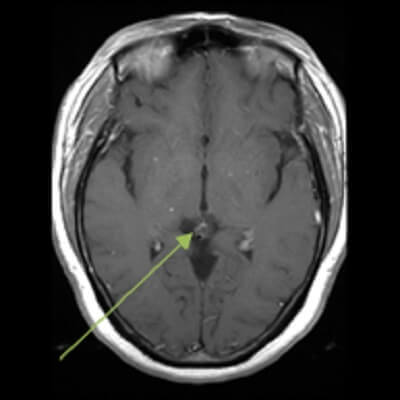

Figure 1: (a,red arrow) axial FLAIR demonstrates a mildly hyperintense pineal mass which is hyperintense on T2 (b,blue arrow) and which has a thin rim of contrast enhancement (c, green arrow).

Pineal cyst is by far the most common pineal lesion. Pineal cysts displace pineal calcifications, are generally less than 10 mm, have homogenous T2 hyperintense signal iso to slightly hyperintense to CSF on MRI and mildly hyperintense on FLAIR. Pineal cysts typically demonstrate thin walled enhancement, although nodular or thicker enhancement of the wall is possible and the central cystic area may fill in with contrast on delayed imaging. The normal enhancing pineal gland may also be seen, typically posterior to the cyst. Differentiating between a pineal cyst and a very indolent pineoblastoma can be a diagnostic challenge; however, pineal cysts are far more common and cysts with classical features are incidental findings that do not require treatment or follow up.